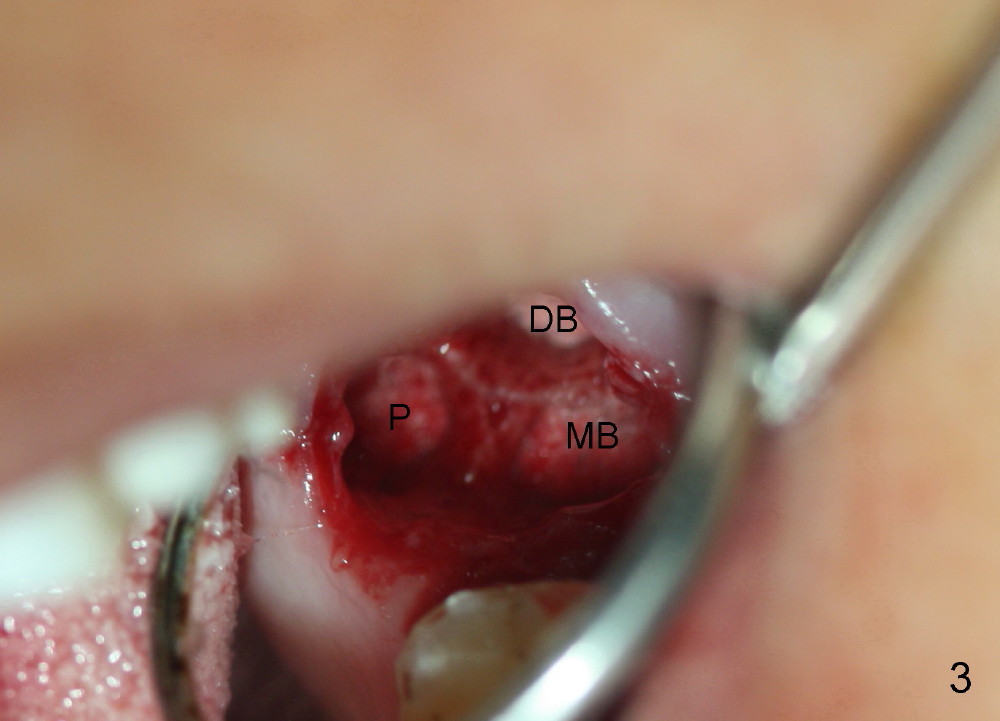

A 57-year-old lady presents for abscess buccal to the tooth #15 (Fig.1 A). Mesial and distal to the occlusal composite (Fig.2 C) is a crack line. In addition to long furcated roots, the upper border of the bone is not shown in this preop PA (arrow). Fig.3 is taken to show a thin septum surrounded by the mesiobuccal (MB), distobuccal (DB) and palatal (P) sockets (Fig.3). Osteotomy is initiated in the septum by 1.2 and 1.5 mm pilot drills, followed by 2,3,4 mm rounded tapered osteotomy at the depth of 17 mm. Nose blowing test is carried out after each step with negative result. Stability is achieved when a 4.5 mm tap is inserted at 17 mm, but the upper end of the tap is not visible (Fig.4,5). When a 5 mm tap is placed, stability is decreased, probably because the coronal end of the septum starts to break down (due to expansion). To re-gain stability, the 5 mm tap needs to go deeper. A 6 mm tap also achieves satisfactory stability at 20 mm. When the tap is removed, there is no air leakage. A 6x20 mm implant is placed with insertion torque > 60 Ncm; the upper end of the implant is still out of view in PA (Fig.6). Another problem is that the implant needs to go deeper to obtain sufficient occlusal clearance. The lower first molars and the 2nd premolars are missing. A panoramic X-ray has to be taken to show the apical end of the implant: ~ 3 mm into the sinus (Fig.7 ^). The maxillary tuberosity appears to grow downward (arrow). In other word, the tooth #15 appears to have been intruded due to overloading.